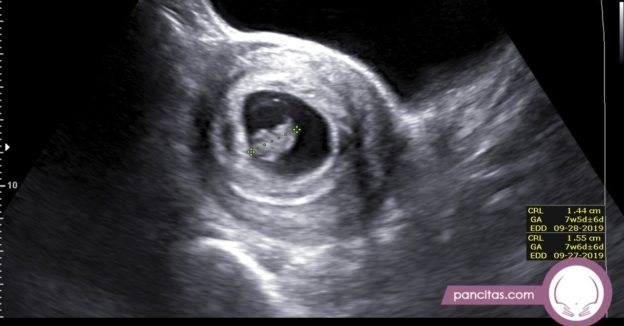

Early Pregnancy Ultrasound

The best time to see your baby’s face in 5D/HD is between weeks 25 and 30 of your pregnancy.

Often referred to as 5D, HD or FRV (fetal realistic view), 5D/HD is the newest development in pregnancy imaging. It captures and combines high definition volume data to create automated images with amazing color and clarity so you can see your baby as though you were looking from inside the womb.